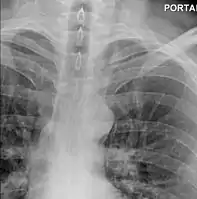

Upright chest radiography showing mediastinal air adjacent to the aorta and tracking cephalad adjacent to the left common carotid artery. This patient presented to the Emergency department with severe chest pain after eating.